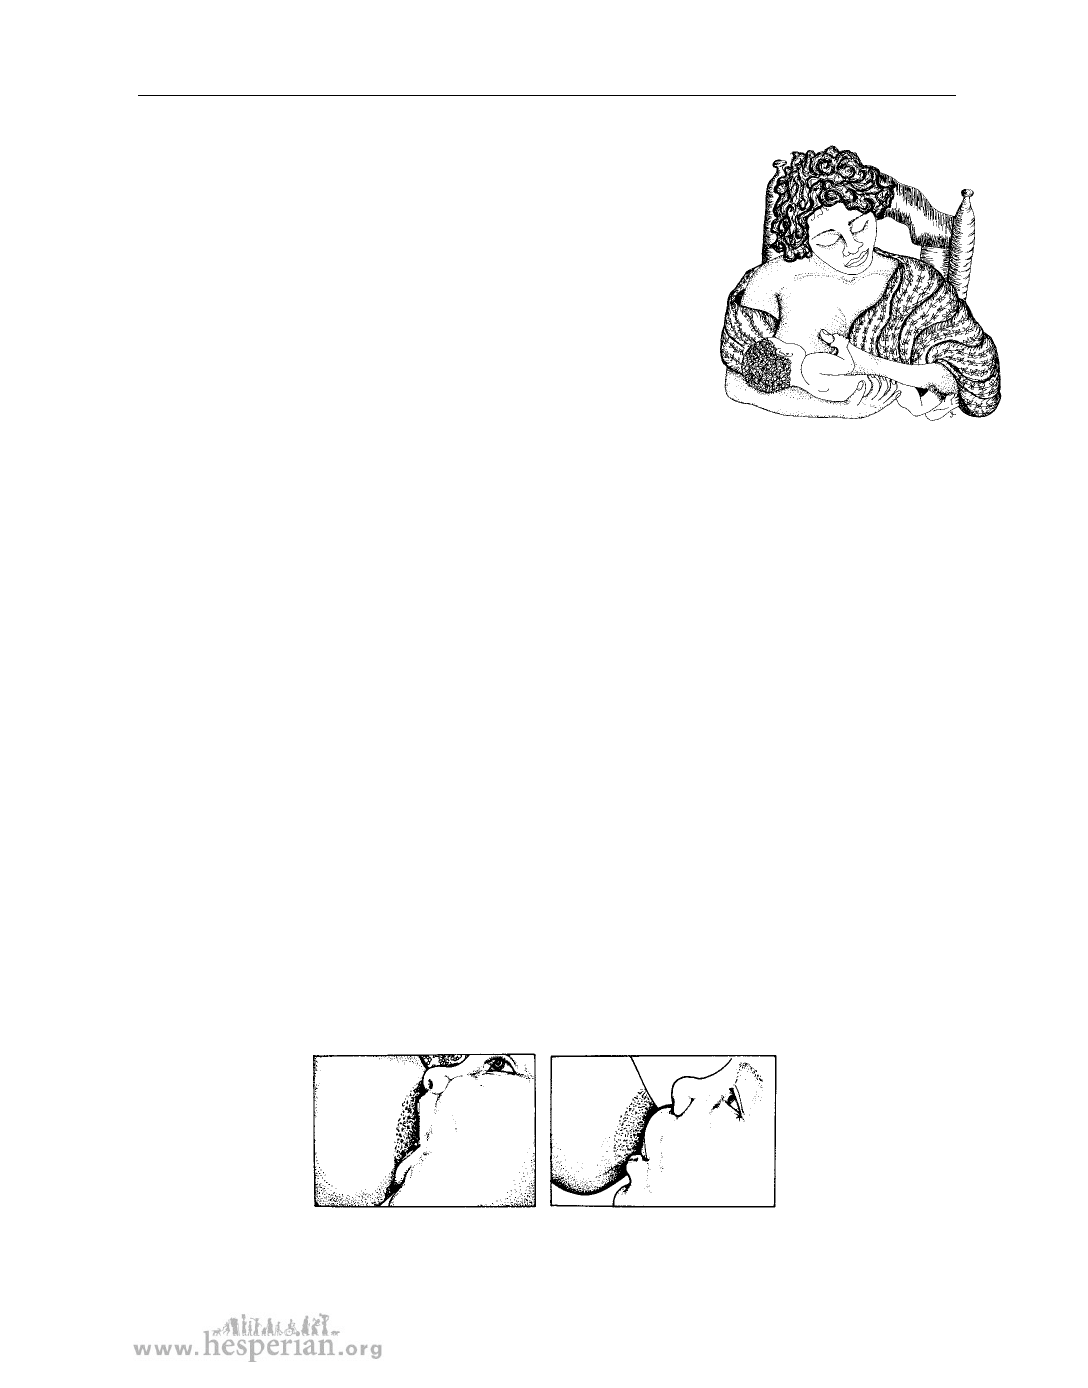

How to breastfeed

Most babies are born knowing how to suck. But they may need help getting enough

of the nipple in the mouth. The baby should have a big mouthful of the breast with

the nipple deep inside.

This baby

has a good

mouthful

of breast.

This baby

does not have

enough breast

in its mouth.